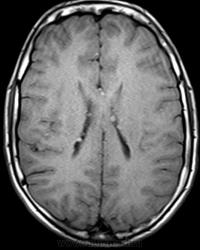

Это болезнь Бурневилля - одна из форм факоматозов?

Да, это болезнь Бурневилля-Прингла, один из видов факоматоза. Врожденное заболевание, развивается из-за нарушений в одной из хромосом.